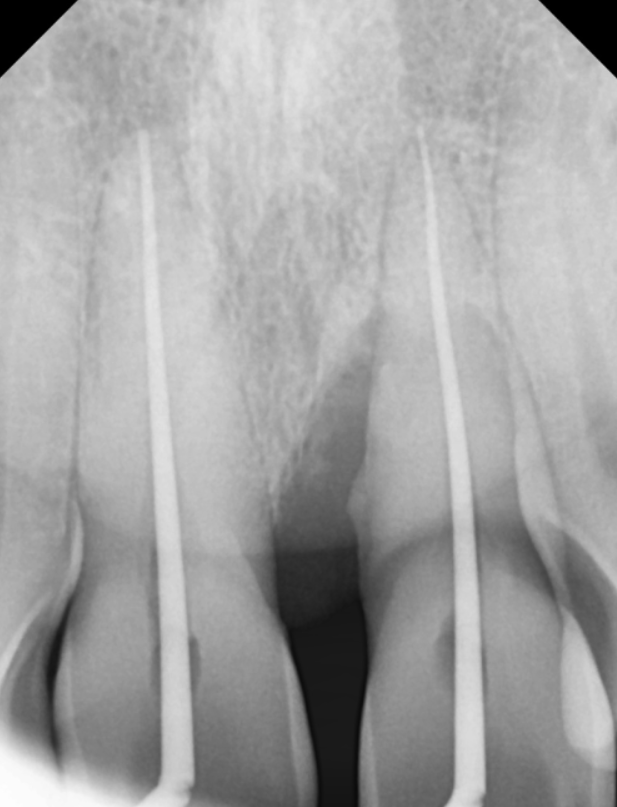

뼈를 녹인 치석들을 제거하고 염증 조직들을 꼼꼼하게 제거한 뒤

잇몸을 다시 건강하게 회복시키는 것이 목표.

또한 치아 뿌리가 드러나 마모된 상태였고

시린 증상이 있어 신경치료를 함께 진행했습니다.

230417 신경치료

그 후 치아 벌어짐과 깨진 부위를 개선하기 위해

옆 치아와의 크기 분배 과정을 거쳐

지르코니아 크라운으로 마무리했습니다.